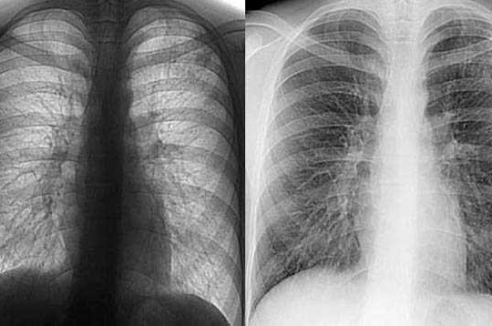

Швейцарцы курят все реже | Les Suisses fument de moins en moins

Благодаря антитабачной кампании и новому законодательству, запрещающему курение в общественных местах, Швейцарии удалось снизить процент курильщиков. И это не предел.